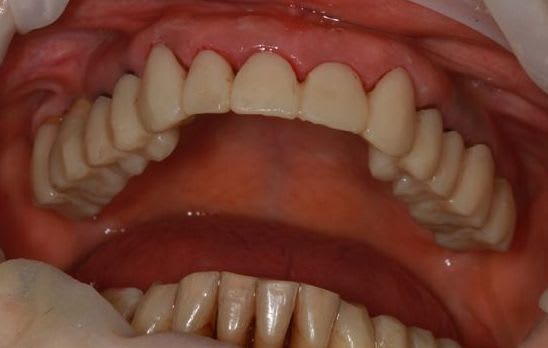

dépose des ceramo métal antérieur, ouf le précédent n'a pas mis d'IC, j'ai plus de marge de manœuvre.

Prochaine étape réalisation d'un provisoire résine "complet" pour le max.sup., mais il me faut paralléliser tous les moignons.

ça commence à sentir bon, dans un premier temps, les provisoires sont en place sans collage (ça marche aussi sur les dents naturelles,pas que sur les implants) pour valider la partie mécanique et permettre aux différents moignons de se positionner bien parallèle, dommage qu'il n'existe pas de "guides" pour ça...

prochaine étape collage des provisoires haut et bas, et mise en attente 1 à 2 mois.